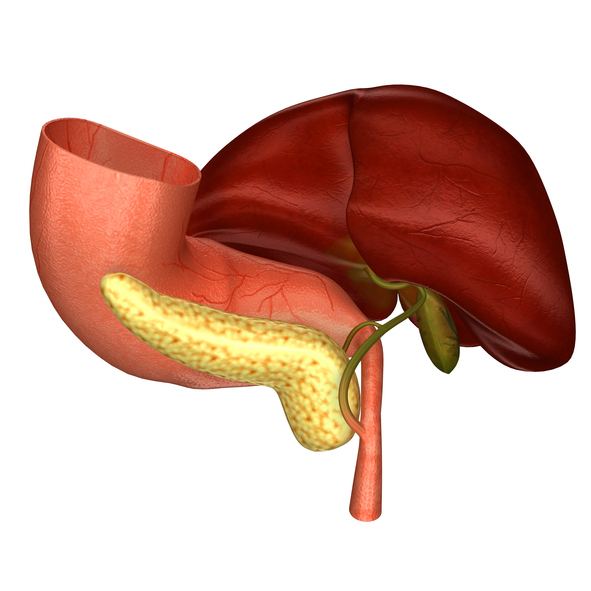

Bile is produced by the liver and is used to aid in proper digestion. It helps the body eliminate waste from the blood. The salts found in bile can emulsify fat and break it down into smaller particles. Bile can help the body absorb those broken down products of fat within the gut. As mentioned, bile is ...click here to read more